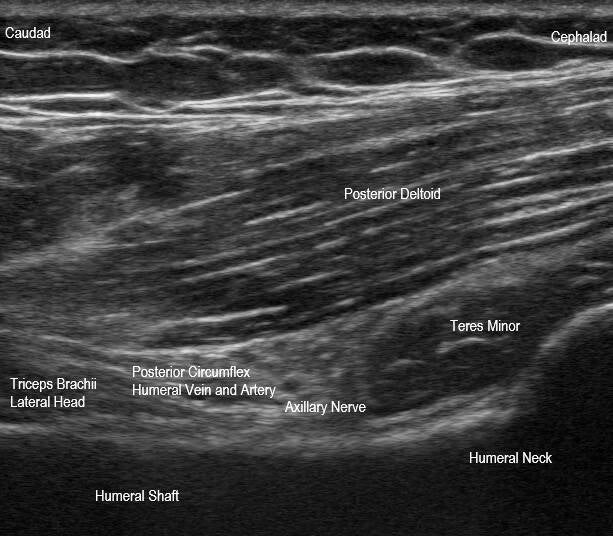

This is an anatomic sagittal plane image of the quadrilateral space, posterior to the teres major. The quadrilateral space contains the posterior circumflex humeral vasculature and axillary nerve. Its boundaries include the teres minor superiorly, teres major inferiorly, long head triceps brachii medially, and surgical neck of the humerus laterally. In rare circumstances, the neurovasculature can become compressed in quadrilateral space syndrome, which can result in posterolateral shoulder pain. In this image, interventions can be performed such as an axillary nerve block, which is typically performed in-plane in a cephalad posterior to caudad anterior approach.